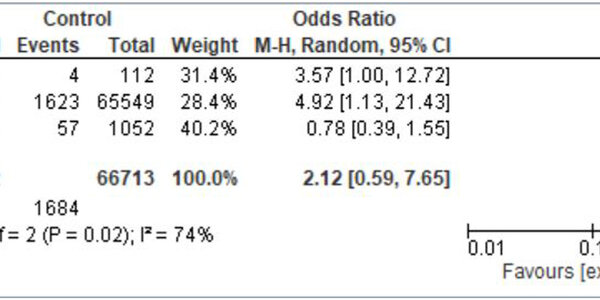

Over 50,000,000 Americans get subsidized or free health under the Affordable Care Act but that doesn't mean usage of preventive care increased across the board. Instead, a new analysis found that the...